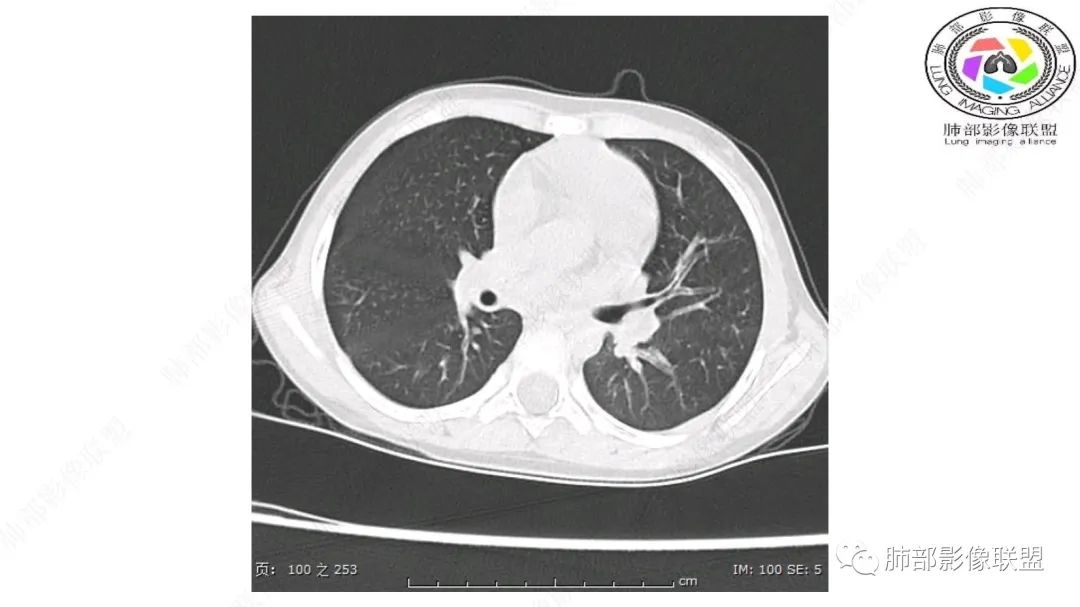

患儿3岁 咳嗽检查发现纵隔占位。右肺上叶受压表现,占位以脂肪组织密度为主,似见分隔,首先考虑为脂肪母细胞瘤,鉴别脂肪瘤,畸胎瘤。

幼儿,右上纵隔团块状脂肪密度影,边缘清晰,内可见血管及支气管穿行,考虑脂肪瘤,鉴别畸胎瘤。

幼儿,右上纵膈团块,脂肪密度,内见分隔,增强病灶内见血管穿行,结合患者年龄,考虑脂肪母细胞瘤,鉴别脂肪瘤。

定位:肺内?尖段气管未见明显显示,腔静脉受压向右推移?病灶内可见前段动脉穿行,脂肪密度为主。

肿块起源于右上气管分叉处?强化动脉血管最后汇入右肺动脉上干。

右侧纵隔奇静脉水平起源?压迫上肺,包绕动脉?

跨肺门,包绕肺血管分支,邻近肺组织受压肺不张。

病灶属于交界区,主体位于肺内,占位效应明显,前方突入胸壁,胸腺受压变形,胸膜显示欠清楚;病灶包绕上叶肺动脉;似乎有体动脉供血。符合肺内的点:包绕上叶肺动脉分支;符合纵隔的点:前方似乎突入胸壁,与胸腺关系比较密切,但是与上腔静脉的关系提示病灶不支持纵隔来源,前纵隔的常规会将上腔静脉受压后移、外移,这是不符合的。

2.肺动脉穿行也许是肺内来源最重要支持点!